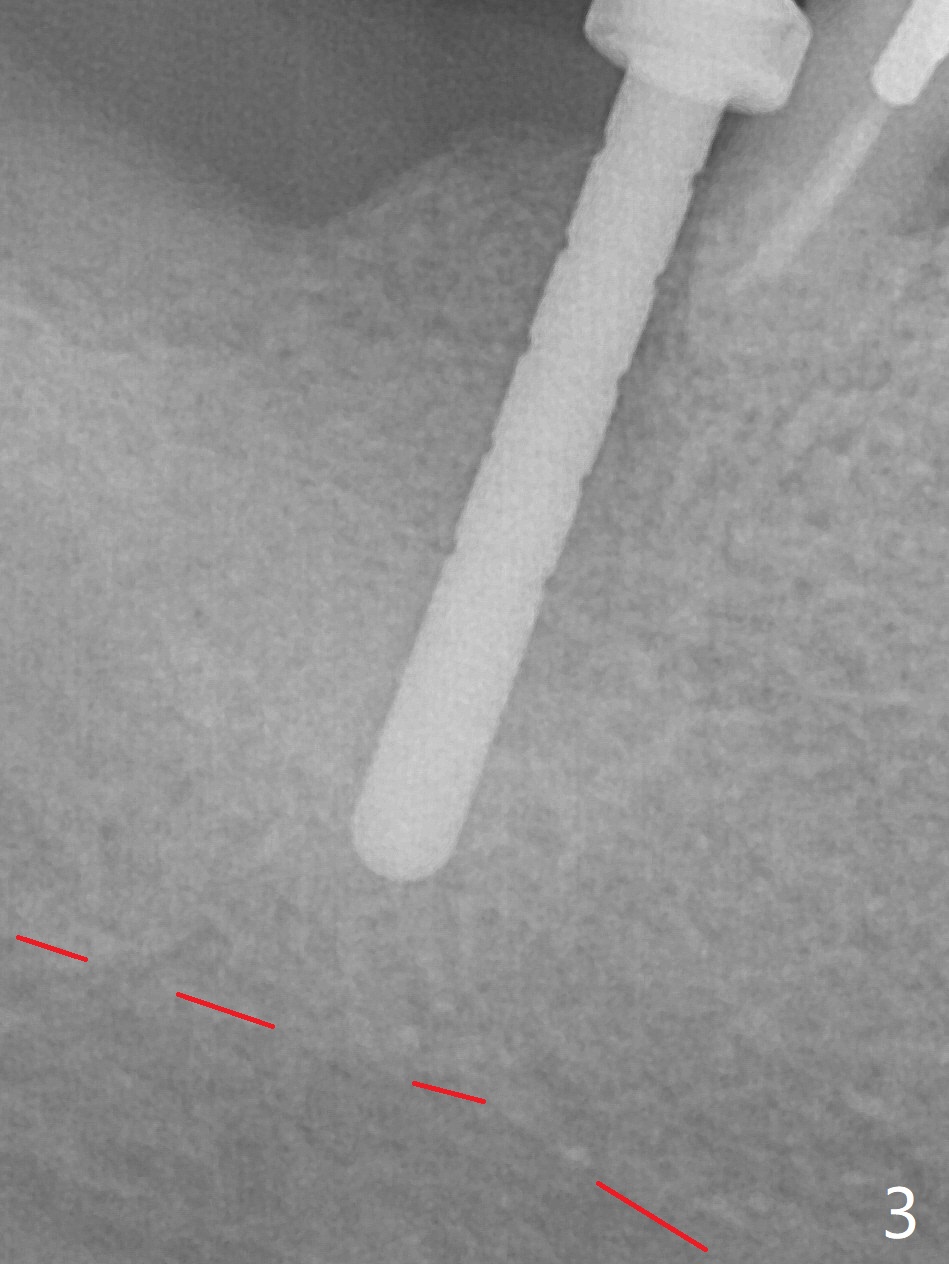

After extraction of the 2nd molar with buccal fistula (Fig.1), osteotomy is initiated beyond the socket for 4 mm (Fig.2,3). Following moving the osteotomy distal and sequential osteotomy, a 4.5x11.5 mm dummy implant is placed equicrestal buccally (Fig.4 ^) with stability; the dummy abutment is 6.5x5(4) mm. A 5x11.5 mm (definitive) implant achieves .>20 Ncm insertion torque (Fig.5). With placement of a 6.5x4(5) mm abutment, Vanilla (Fig.6 *) and Osteogen plug over the graft and in the socket of #32, periodontal dressing is applied. The implant at the 2nd molar placed much deeper than the 1st molar seems to be risky in term of the Inferior Alveolar Canal (Fig.3-6 red dashed line). Several carpules of anesthetics have to be administered in an infiltration manner for pain control. Fortunately there is no postop paresthesia. For an un-compliant patient, socket preservation is a better option. The implant seems to have osteointegrated 4 months postop (Fig.7).